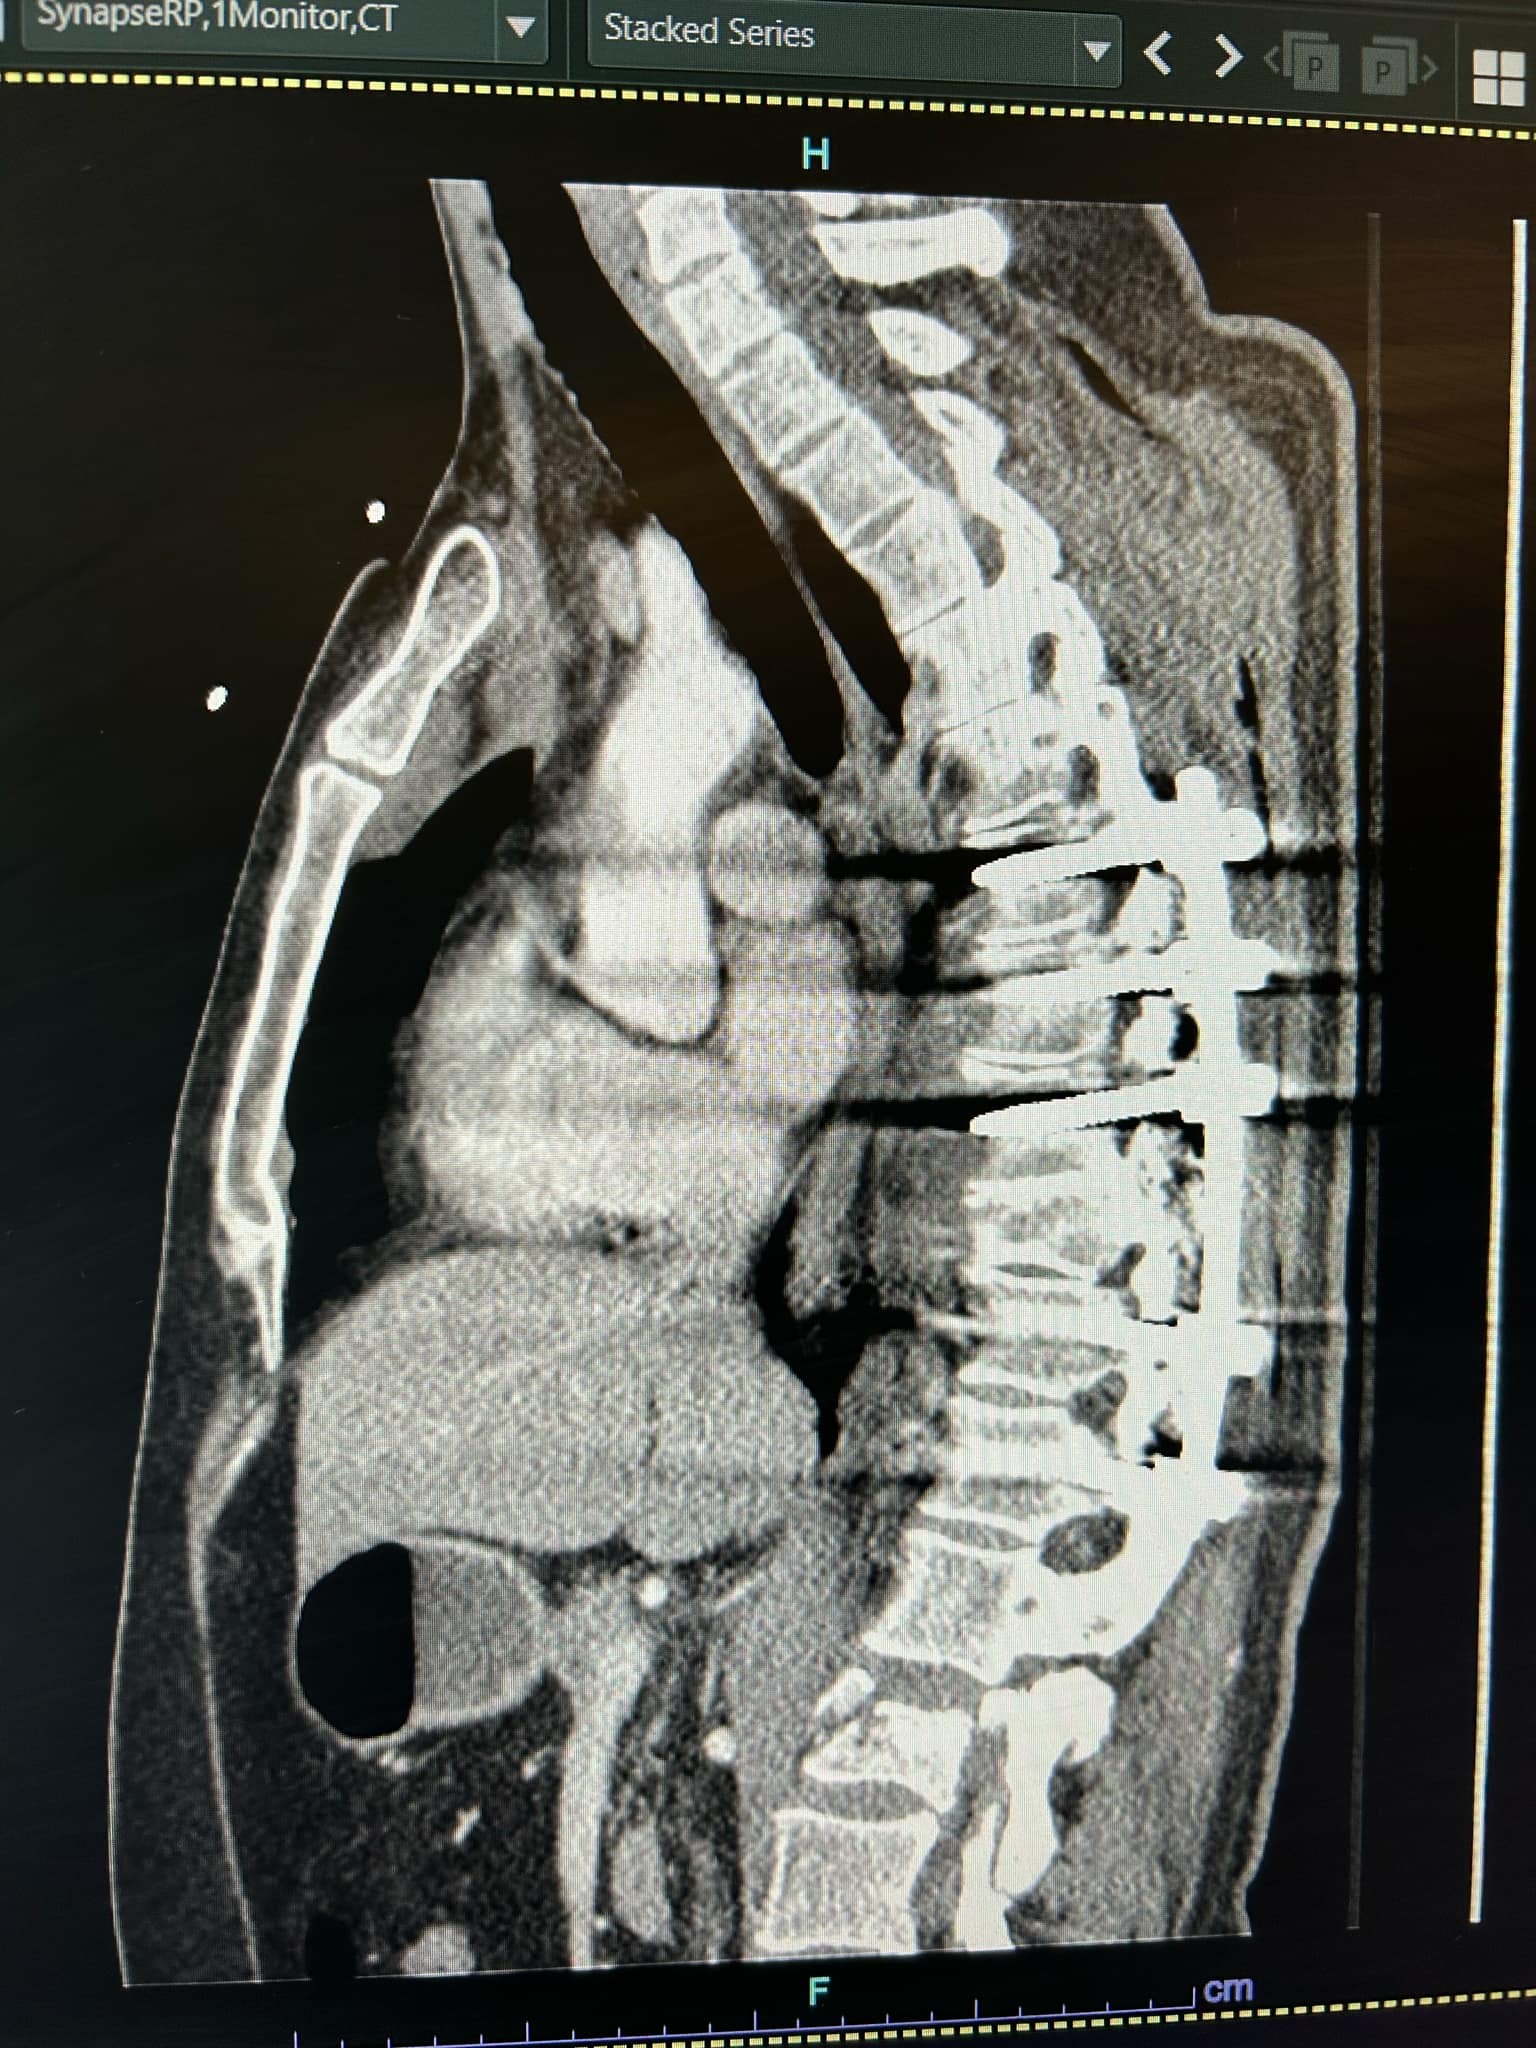

On April 28th, my partner Erick was in a serious mountain biking accident. He suffered a burst fracture in his spine (T1), a shoulder broken in three places, and eight fractured ribs. He’s already undergone emergency spinal surgery (a four-level fusion), and the recovery ahead will be long and intense—expected to take at four to six months, with physical therapy, follow-up scans, and a lot of healing time at home.